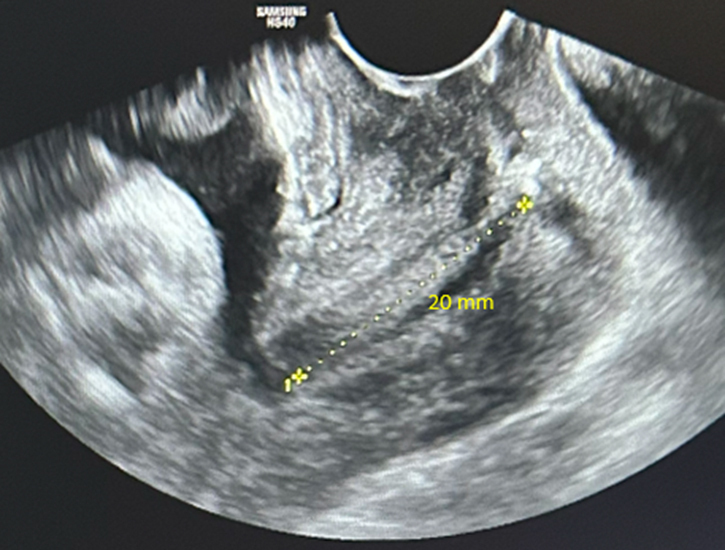

Voici le résultat de la cardiotocométrie et de l’échographie du col réalisée par voie endovaginale.

Figure 5 (Rodolphe Matias de Sousa, La Revue du Praticien)

Une menace d’accouchement prématuré se définit comme des contractions utérines régulières et douloureuses (ici 5 par dix minutes visibles à la tocométrie) et un col raccourci ou modifié cliniquement (ici mesuré à 20 mm à l’échographie endovaginale). Un col non modifié est dit long, tonique, postérieur, fermé avec une présentation fœtale non sollicitante.

Concernant l’échographie endovaginale.

Figure 7 (Rodolphe Matias de Sousa, La Revue du Praticien)